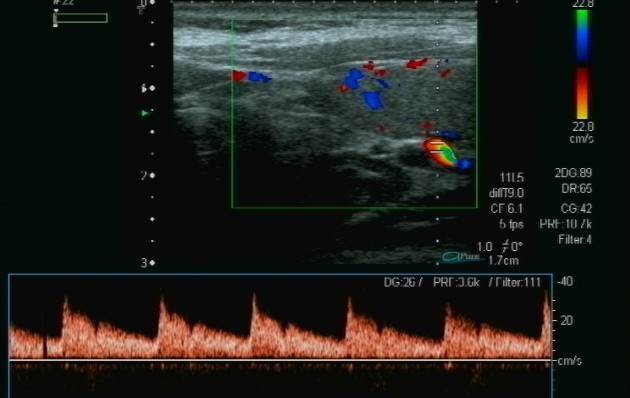

Oltre all'ecografia gastrointestinale, l'ecografia tiroidea rappresenta un altro campo specialistico di vasta esperienza con esecuzione della diagnostica base, il colordoppler e doppler tiroide e lo studio elastografico delle lesioni nodulari tiroidee altrimenti detta elastografia. Questa metodica permtte lo studio della elasticità dei tessuti e considerando che i tessuti neoplastici tendono ad essera di consistenza aumantata, l'elastografica ci aiuta a selezionare i noduli da sottoporre ad campionamento citologico con FNAB.